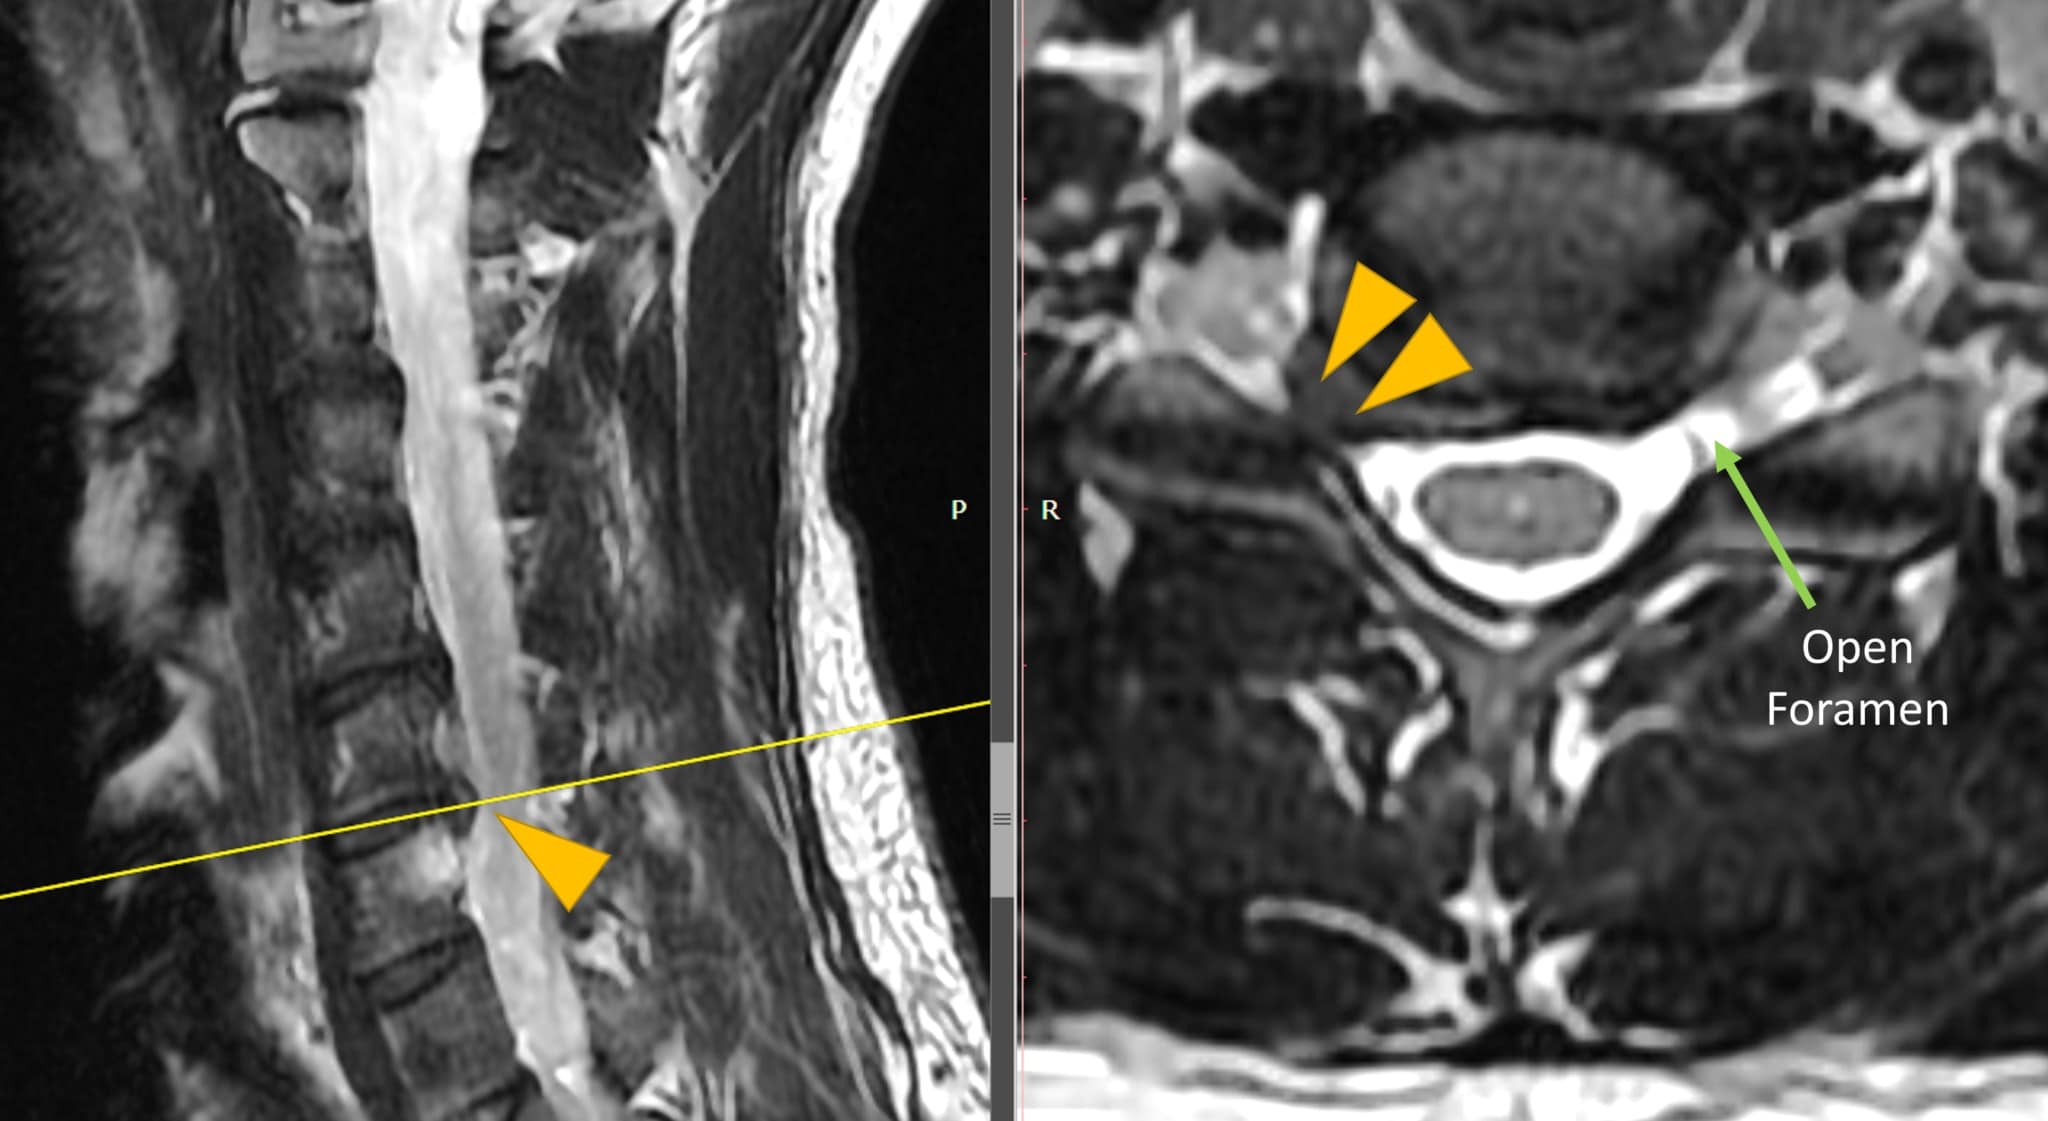

From motionlit.com

Cervical Disc Bulge Injury MRI Interpretation MotionLit Cervical Disc Bulge Reddit It is the worst, most painful thing i’ve ever been through. looking into the disc replacement as i do not have disc height issue nor mylopathy. a bulging disc in the neck occurs when a spinal disc weakens and encroaches on the spinal. until i found the right person (neurosurgeon) to look at my cervical spine mri. Cervical Disc Bulge Reddit.